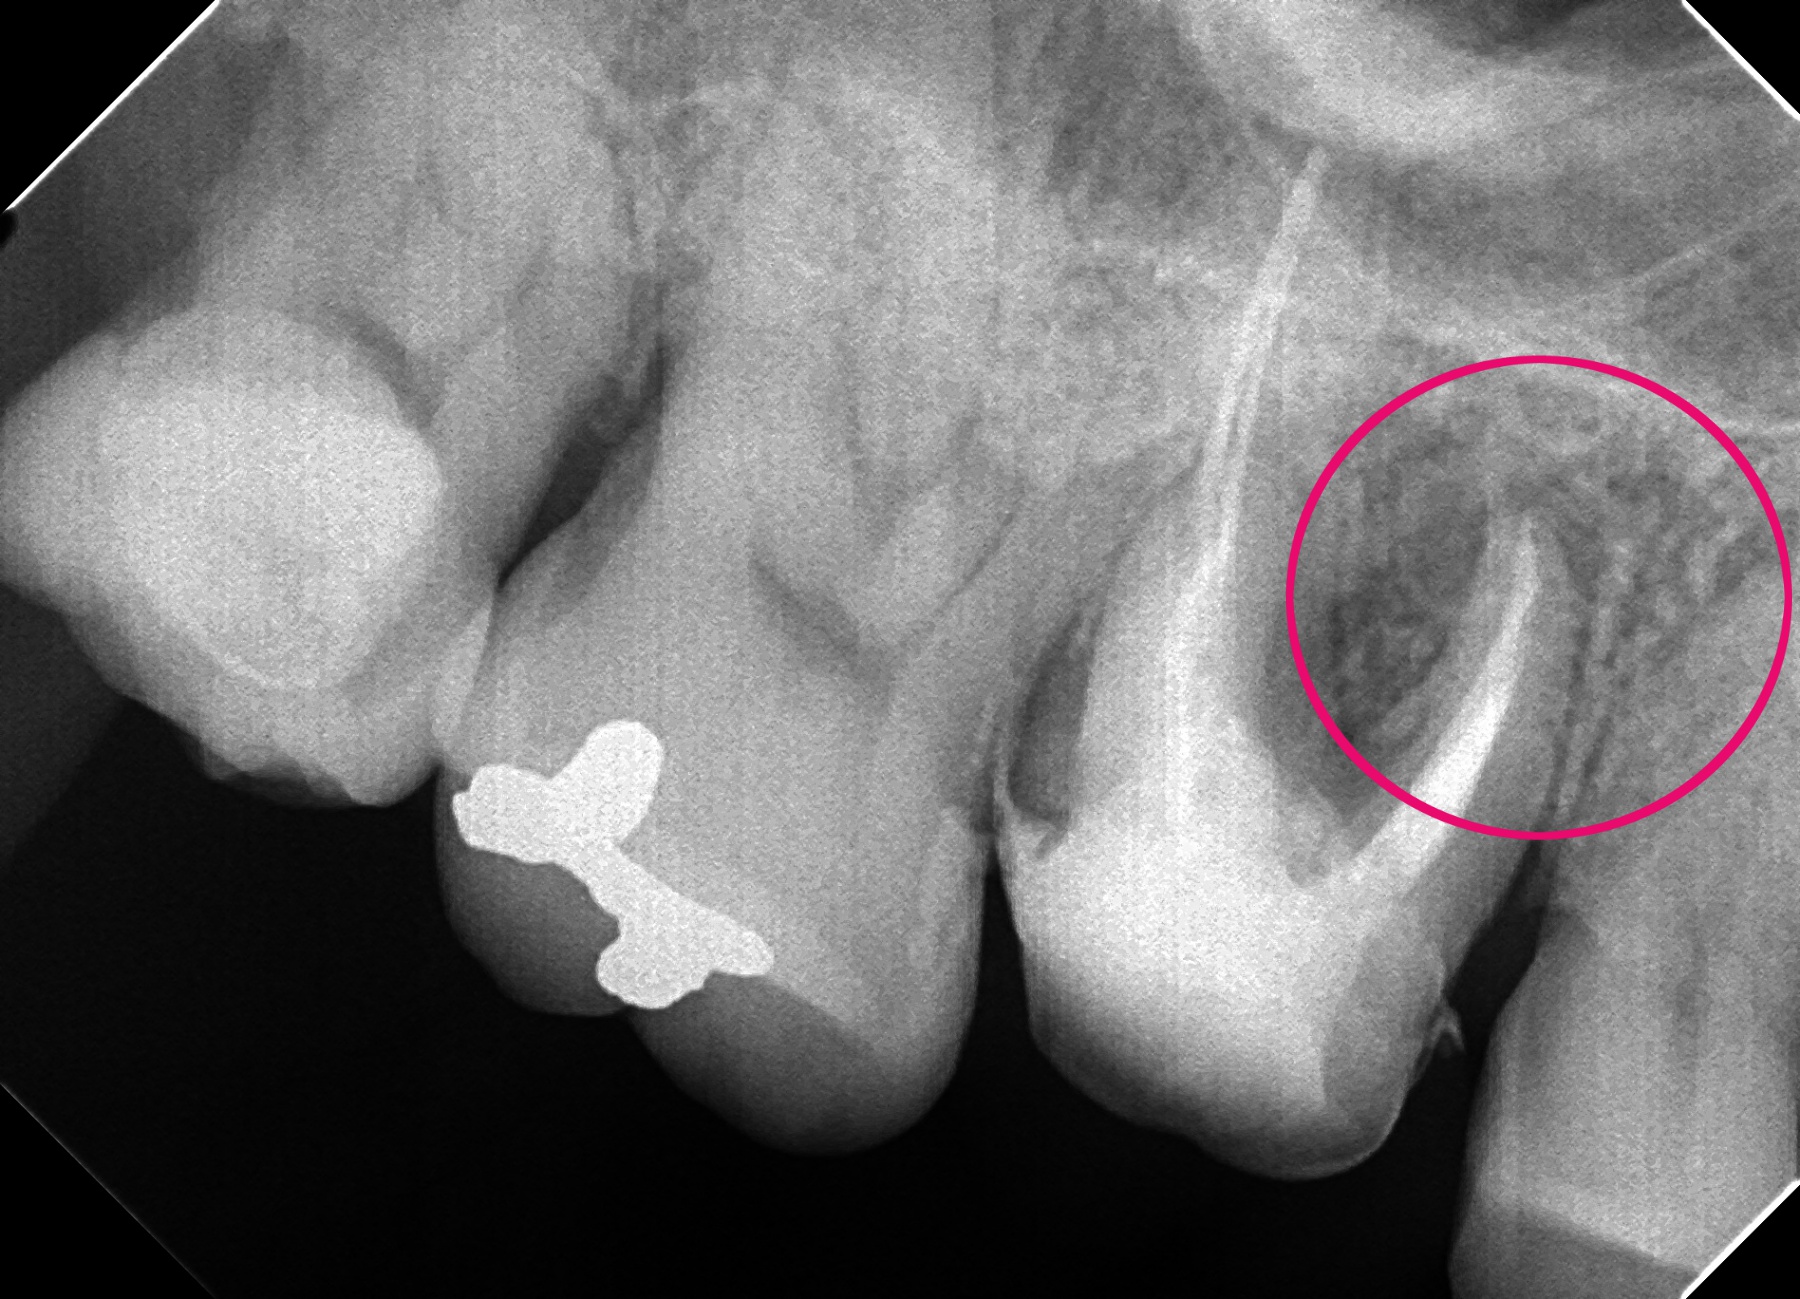

歯の根の先にうみが貯まり、レントゲンに黒く映っています。

根の先が菌に感染してうみが貯まると、うずいたり、痛みが出る可能性があります。

(他院で以前治療した歯の根の先が腫れた。)

うみを神経の通っていた管を通して出し管を消毒します。

管がきれいになったら根の先まで蓋をする薬をいれ、再び菌が入って感染するのを防ぎます。当医院では根の治療の回数や時間をかけますが、一本一本確実な治療を心がけています。